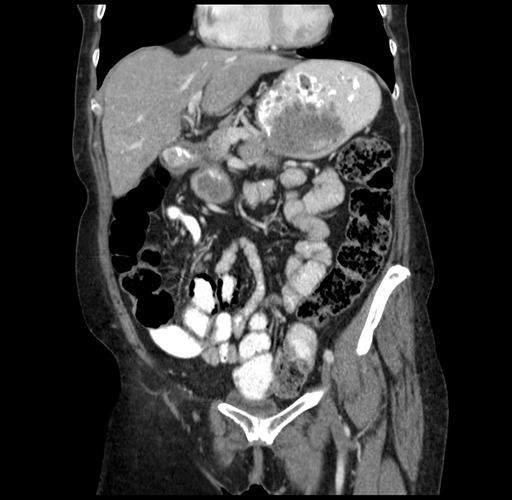

Axial Venous